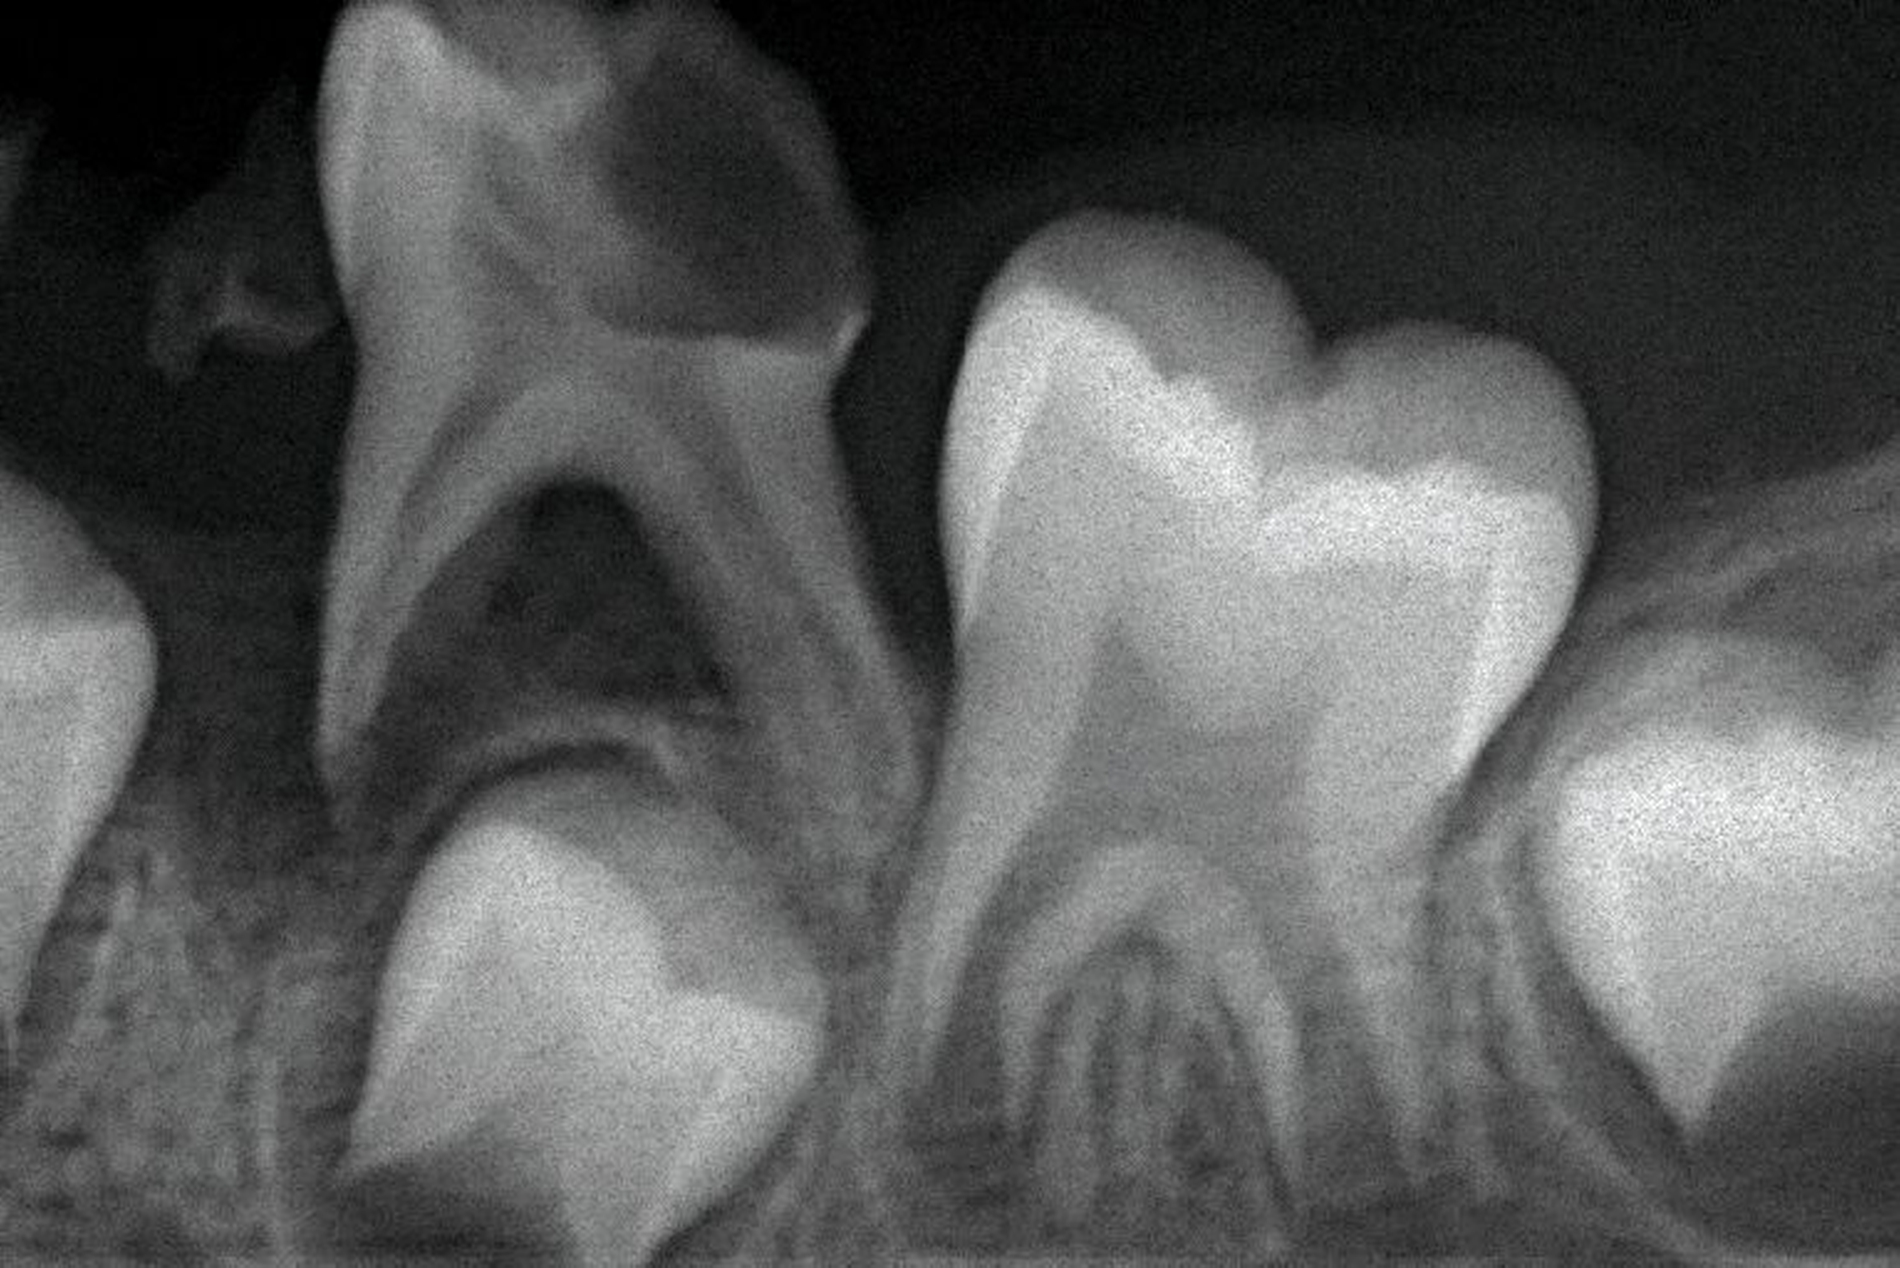

Gerade in der Kariesentfernung hat sich in den vergangenen Jahren eine bemerkenswerte Verschiebung ergeben: Die Hall-Technik hat erfolgreich gezeigt, dass bei einem dichten Verschluss eigentlich überhaupt keine Entfernung von kariös verändertem Schmelz oder Dentin notwendig ist. Auch bei der Kariesinaktivierung ist in der Regel keine Kariesentfernung nötig, gegebenenfalls ein Aufschleifen der Läsion zur besseren Reinigungsfähigkeit (Abbildung 3). Und selbst bei restaurativen Techniken wurde die Idee vom „sauberen, keimarmen Restdentin“ und zusätzlicher „Kavitätentoilette“ zur weiteren Keimreduktion verlassen und durch die selektive Kariesexkavation mit primär kariesfreien Kavitätenrändern zur adäquaten Verankerung einer Restauration ersetzt.

Die Kariesinaktivierung von approximal kariösen Läsionen bei Milchzähnen ist schwieriger, da diese in der Regel nicht gut für die tägliche Mundhygiene zugänglich sind. Daher können diese Läsionen für eine Kariesinaktivierung in der Zahnarztpraxis oberflächlich rotierend eröffnet werden (Abbildung 3), um dort eine manuelle Plaqueentfernung durch das Zähneputzen und Fluoridierungen zu Hause beziehungsweise in der Praxis zu ermöglichen. Ferner erhalten die Eltern exakte Mundhygiene- und Ernährungsinstruktionen sowie eine effektive Motivation zur entsprechenden Umsetzung. Das beinhaltet auch ein Putztraining und Anwendung von Techniken im Rahmen der sprechenden Zahnmedizin wie „motivational interviewing“ [Miller und Moyers, 2017]. Bei dieser nicht-restaurativen Kariestherapie wird im Gegensatz zu den Standardfüllungen das Kariesmanagement bewusst auf die Patientenebene verlagert, da nur durch die manuelle Störung des Biofilms (also das Putzen) der chronische Kariesprozess gestoppt werden kann und somit eine Inaktivierung von Karies erfolgt [Kidd und Fejerskov, 2013]. In diesem Falle ist nicht zwingend eine restaurative Therapie notwendig, kann aus ästhetischen oder funktionellen Gründen aber sekundär bei inaktiven Läsionen erfolgen.